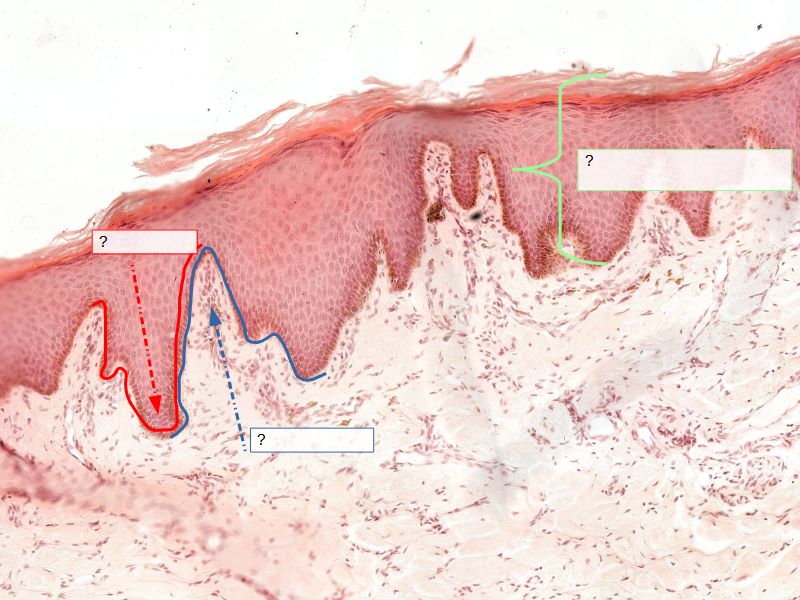

Fill in all the missing labels, and assess as you move through the slides. Answers on the down slide. It is important to do this using pen and paper, and not just glance through the images.